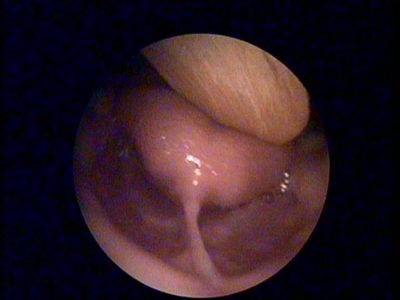

Dil bağı muayenesi nasıl yapılır, dil bağı nasıl farkedilir, dil bağı belirtileri ...

Yenidoğanda dil bağı görülür mü? dil bağı kalınlığı ...